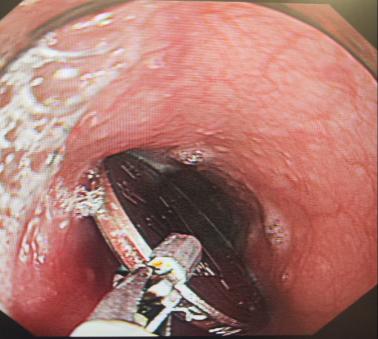

第二步:立即就醫(yī)內(nèi)鏡中心是首選??捎秒娮游哥R直觀地發(fā)現(xiàn)并取出食道的異物。